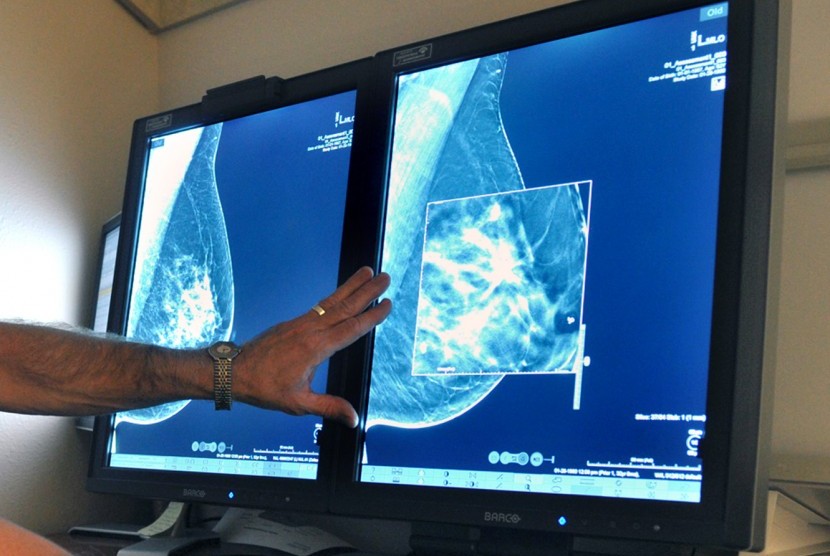

Sistem Kecerdasan Buatan Google Deteksi Kanker Payudara Lebih Akurat Ketimbang Dokter Tiktak Id

Dijital Mamografi Tomokay Tibbi Goruntuleme

Dijital Mamografi Tomokay Tibbi Goruntuleme

Dijital Mamografi Tomokay Tibbi Goruntuleme

Dijital Mamografi Tomokay Tibbi Goruntuleme